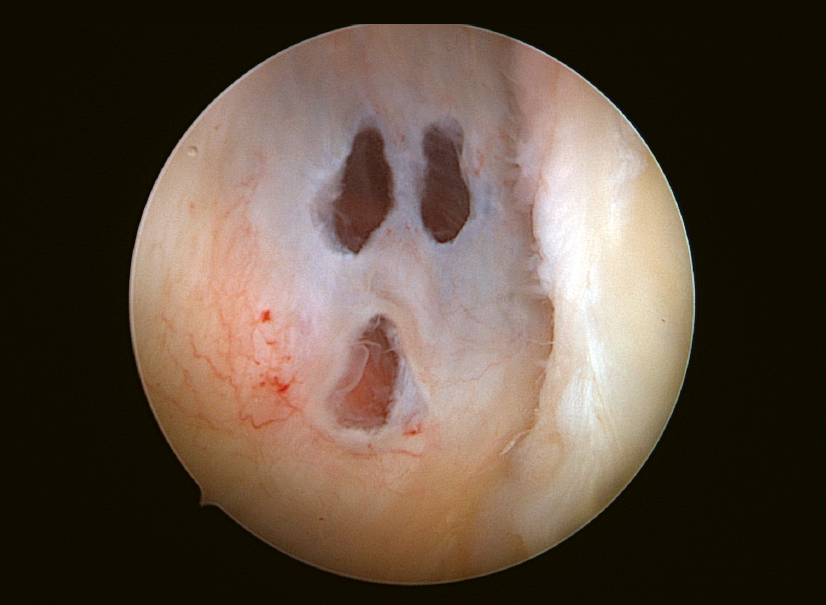

Scream está en el hombro

Scream is in the shoulder

Después de realizar el abordaje artroscópico posterior habitual de un hombro izquierdo con algunas dificultades, colocamos la óptica en el portal anterosuperior para evaluar el labrum posterior y pudimos ver cómo la cápsula posterior había sido perforada en 3 lugares, ofreciendo una gran similitud con el aspecto del fantasma de Scream.